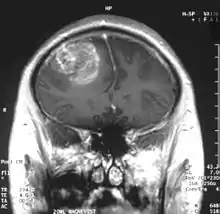

Somasundaram's work is centered around the studies of oncoviruses, tumor suppressor genes, gliomas and microRNAs and he has done advanced research on glioblastoma, an aggressive form of cancer affecting the brain.[8][9] The group led by him is engaged in work concerning the determination of the role of cellular tumor antigen p53 in glioma, regulating the protein, p73 in cervical cancer patients, using Adenovirus early region 1A, a tumor suppressor gene, the analytical study of BRCA1 gene in breast cancer and the analysis and regulation of SV2A, a synaptic vesicle protein.[3] He demonstrated that glioblastoma spreads rapidly by producing macrophage colony-stimulating factor (MCSF) in large quantities which in turn stimulate the growth of blood vessels in the tumor.[10] He proposed that the MCSF interacted with the anti-tumor microglial cells of the human body and induced them to produce Insulin-like growth factor-binding protein 1 (IGFBP1), thereby impairing the capacity of microglial cells to fight the tumor cells, a process he called befriending. The discovery of this new molecule, IGFBP1 and its role in glioma angiogenesis, led to a collaborative investigation which involved four research institutions namely National Institute of Mental Health and Neuro Sciences, Sri Sathya Sai Institute of Higher Medical Sciences and Institute for Functional Genomics (INSERM) of the University of Montpellier, apart from the IISc.[11] The research team led by Somasundaram and Phillipe Marin of INSERM validated the earlier findings and proposed a new therapeutic protocol for glioblastoma which targeted IGFBP1, rather than Vascular endothelial growth factor (VEGF) which earlier treatment methods attacked.[12] The researchers, later, released their findings through a paper, Glioblastoma-derived Macrophage Colony Stimulating Factor (MCSF) Induces Microglial Release of Insulin-like Growth Factor-Binding Protein 1 (IGFBP1) to Promote Angiogenesis, published in the Journal of Biological Chemistry.[13] Work is in progress at his laboratory for developing biomarkers (twenty genes of which is named gene X, have already been discovered)[14] for which detailed study is being conducted on microRNA, DNA methylation, modifications of chromatin and gene fusions.[4][15] His studies have been documented by way of a number of articles[16][17][note 1] and ResearchGate, an online repository of scientific articles has listed 178 of them.[18] He has also conducted workshops[19][20][21] including the Workshop on Next Generation Sequencing organized by the Council of Scientific and Industrial Research in November 2013[22] and has delivered invited or plenary speeches at various conferences and seminars[23] and the 5th annual meeting of the Proteomics Society, India held in September 2013 was one among them.[24]